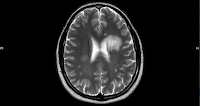

Los factores etiológicos comunes en la Esclerosis Múltiple y las enfermedades cardiovasculares, como la disfunción del sistema inmunológico y la inflamación, pueden explicar en cierta medida estos hallazgos. Se ha documentado en pacientes con Esclerosis Multiple niveles plasmáticos más altos de homocisteína (Ramsaransign GS et al. J Neurol Neurosurg Psyq 2006, Li X et al . Int J Med Sci 2020), factores trombogénicos alterados (Malkki H. Nat Rev Neurol 2016), disfunción endotelial (Sheikh MH et al. J Neuroinflammation 2020) disfunción autonómica cardiovascular (Kaplan T. et al. Neurologist 2015). Se ha sugerido que la inflamación, el estrés oxidativo y los niveles elevados de homocisteína en la Esclerosis Múltiple conducirán a una disfunción endotelial, lo que representa un paso temprano hacia la aterosclerosis.